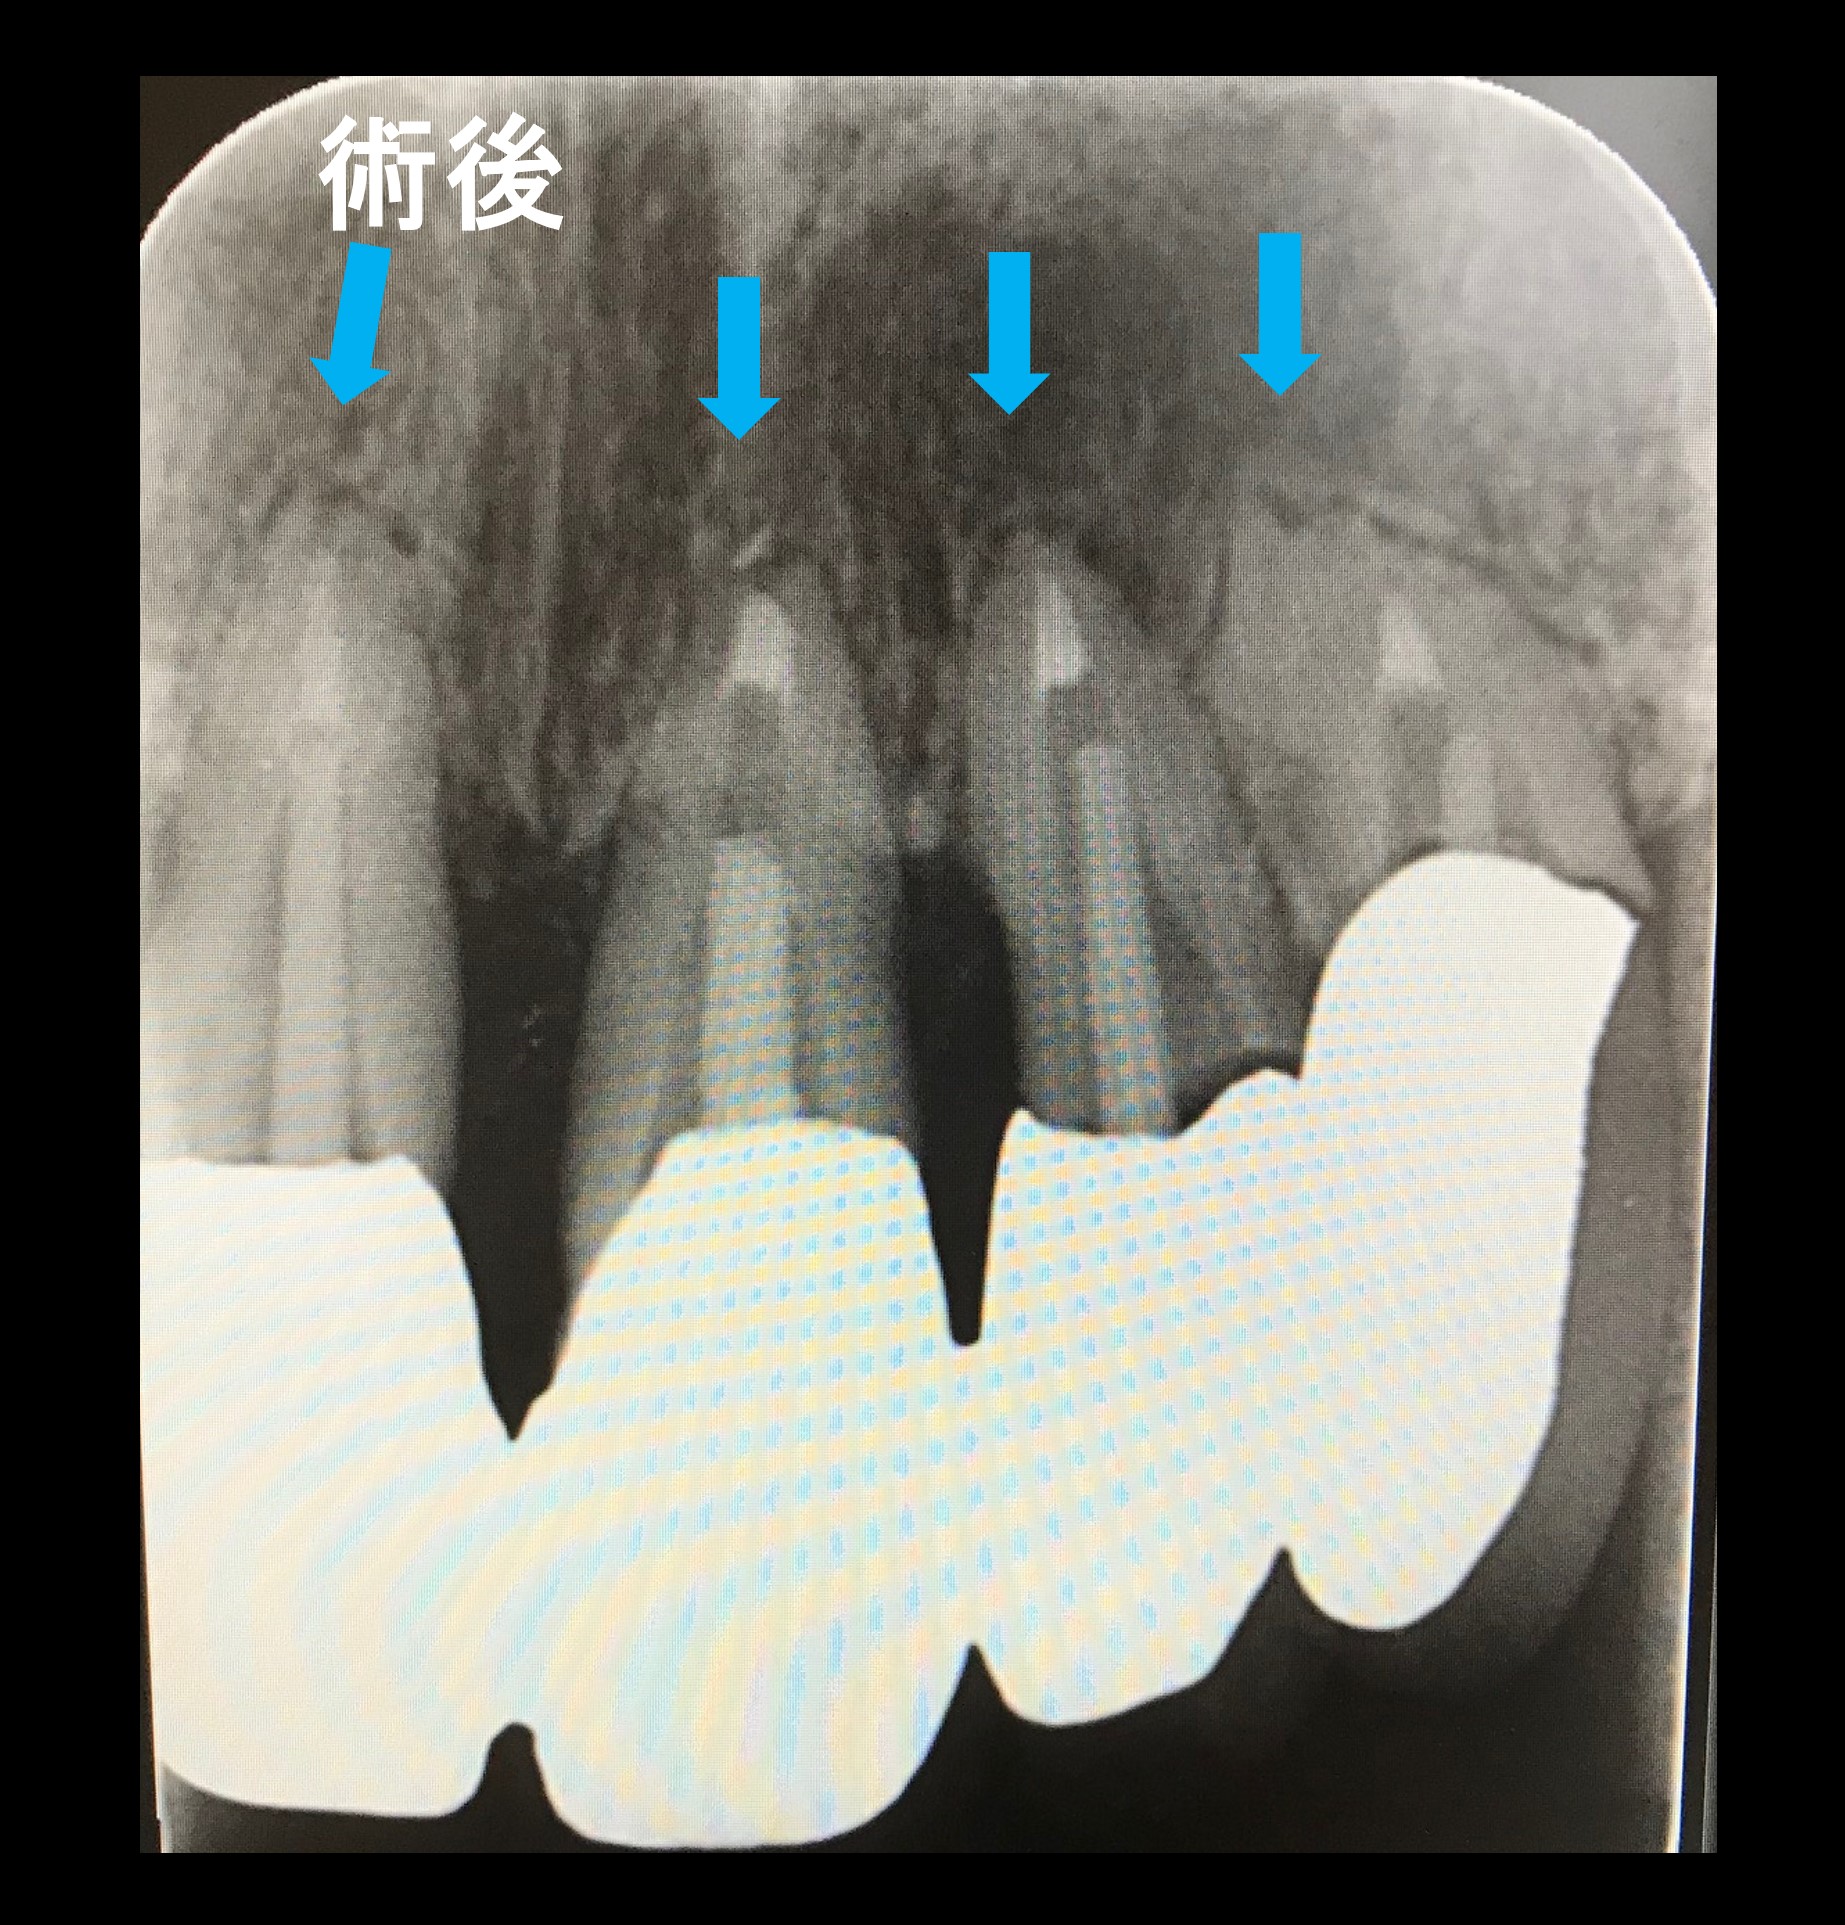

術後写真です。

青矢印に注目すると、根の先にあった黒い影がなくなり骨が再生して良く治っています。